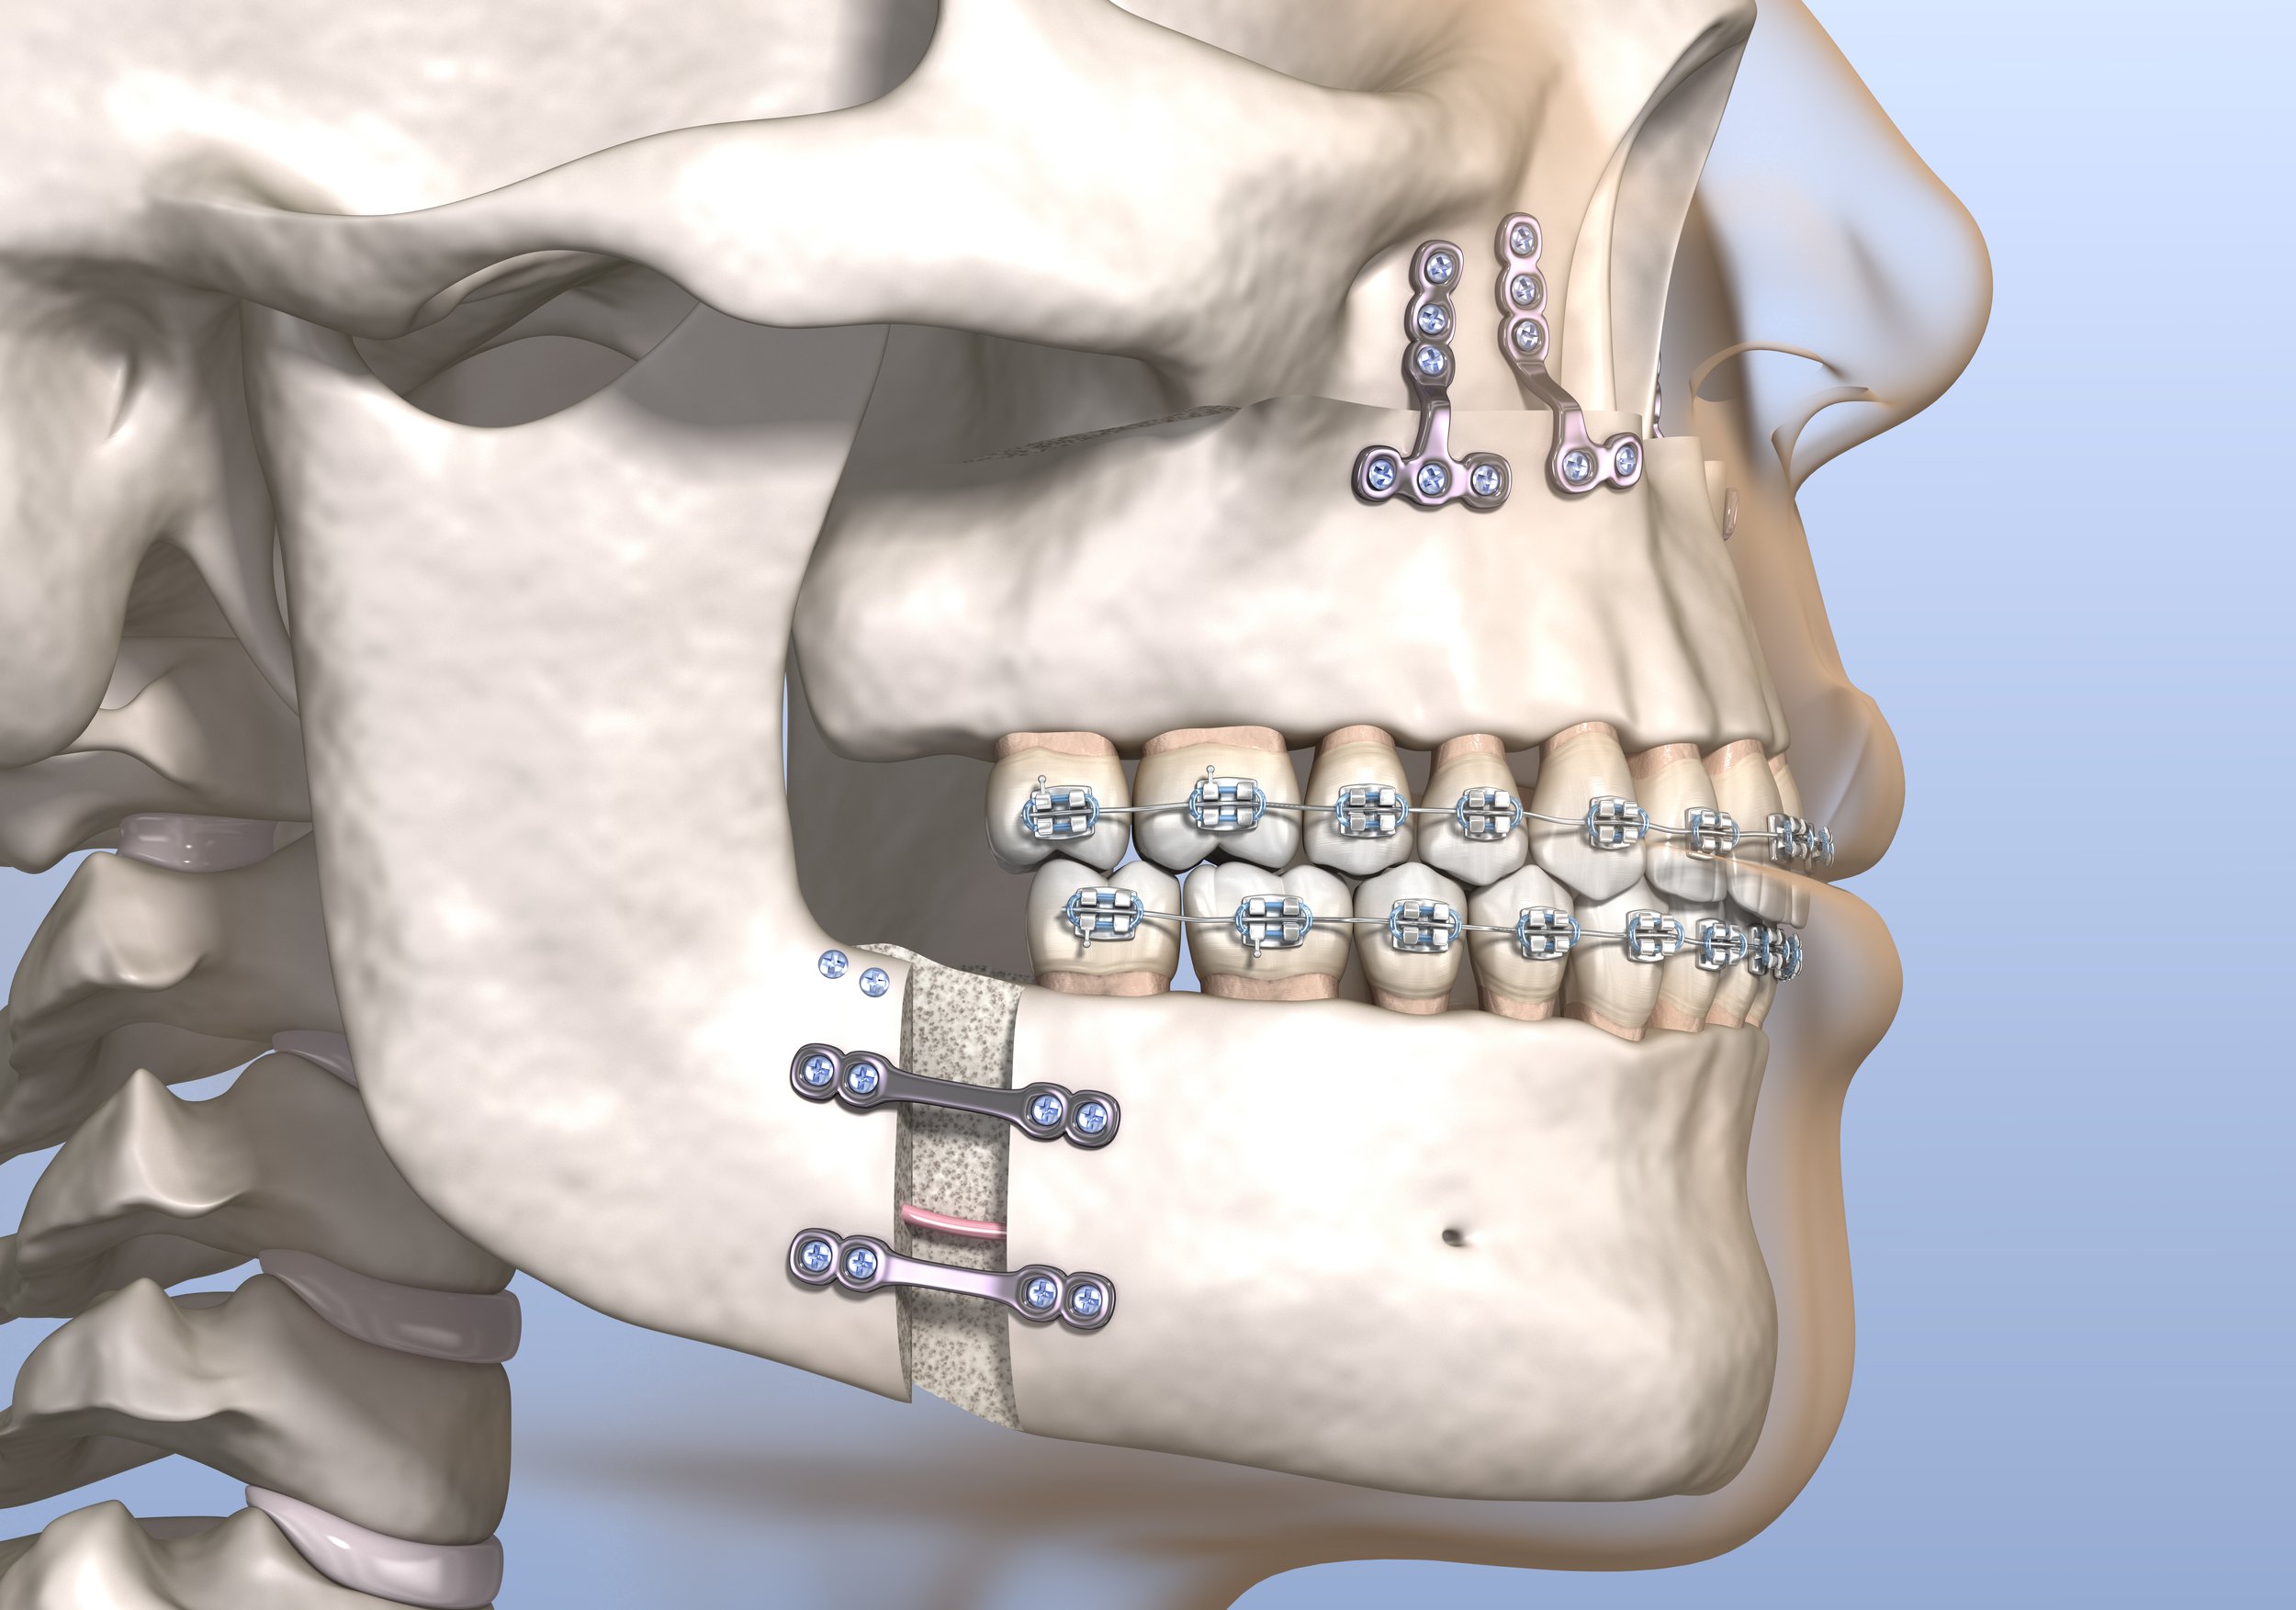

20 Minimally Invasive Orthognathic And Condylar Surgery | Pocket Dentistry

pocketdentistry.comcondylar orthognathic surgery minimally invasive pocketdentistry

pocketdentistry.comcondylar orthognathic surgery minimally invasive pocketdentistry